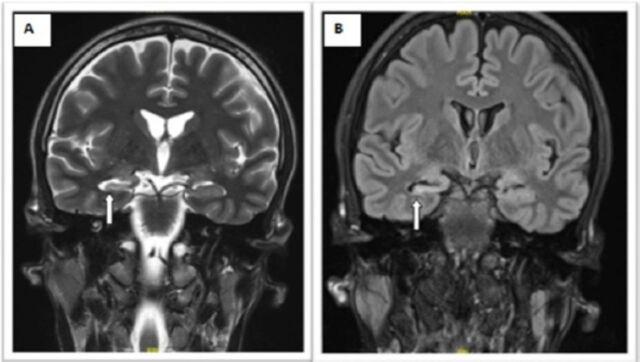

Neuro-vegetative features have been linked to epilepsy arising from the temporal lobe, which can be seen during ictal events and play an important role in determining the focal side of the lesion. Among the rare known features is peri-ictal water drinking (PIWD). Here, we present the case of a 31-year-old male with refractory temporal epilepsy, having episodes of PIWD. The patient was considered a candidate for resective surgery and was investigated accordingly, including long-term video electroencephalogram (EEG), brain magnetic resonance imaging (MRI), and neuropsychology assessment, which pointed towards a lesioned temporal lobe over the non-dominant hemisphere. The patient had an excellent outcome following right anterior temporal lobectomy. The lateralization significance of PIWD has not yet been established definitively in the literature, partly due to a limited number of published cases. This case highlights the previously observed association between PIWD and the involvement of the non-dominant hemisphere in epilepsy patients.

神经植物性功能与起源于颞叶的癫痫有关,这些功能可在发作期事件中观察到,并在确定病变的局灶侧方面发挥重要作用。在已知的罕见特征中有一种是发作期饮水(PIWD)。在这里,我们介绍了一位 31 岁的男性病例,他患有难治性颞叶癫痫,发作期出现 PIWD。患者被认为是可进行切除术的候选者,并进行了相应的检查,包括长期视频脑电图(EEG)、脑磁共振成像(MRI)和神经心理学评估,这些检查指向非优势半球的颞叶病变。患者在接受右侧前颞叶切除术治疗后效果极佳。PIWD 的侧化意义在文献中尚未得到明确确定,部分原因是发表的病例数量有限。该病例突出了之前观察到的 PIWD 与癫痫患者非优势半球受累之间的关联。